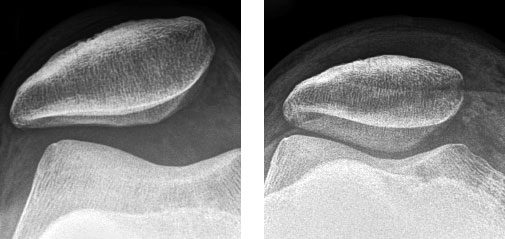

Die häufigsten Ursachen für Hüftschmerzen und Knieschmerzen sind abnutzungsbedingte Veränderungen des Gelenkes sowie auch unfallbedingte Verletzungen  (Knie- und Hüftverletzungen) und Verletzungsfolgen wie beispielsweise Hüftarthrose, Kniearthrose, gelenknahe Knochenbrüche, Meniskusrisse, Kreuzbandrisse.

Behandlungen von Hüft- und Kniegelenksverletzungen und degenerative abnutzungsbedingte Leiden sind eine unserer Spezialitäten, so zum Beispiel Kunstgelenkersatzoperationen an Hüfte und Knie, als auch Knochenbruchbehandlungen insbesondere hüftgelenksnahe Frakturen, Oberschenkelbrüche oder auch Knochenbrüche unter Mitbeteiligung des Kniegelenkes. Eine unserer weiteren Spezialitäten ist die Behandlung von Meniskus- und Kreuzbandrissen. Die Entwicklungen auf diesem Fachgebiet sind enorm vorangeschritten, sodass heute viele Eingriffe in entsprechender arthroskopischer oder minimal-invasiver Technik durchgeführt werden können. Dies führt in der Regel zu bedeutend kürzeren Spitalaufenthalten. Für weitere Informationen wenden Sie sich an unsere Praxis, kontaktieren uns via Kontaktformular oder entnehmen Informationen aus den nebenstehenden Links. Doch was ist eigentlich Arthrose? Lesen Sie auf diesem Link weiter!